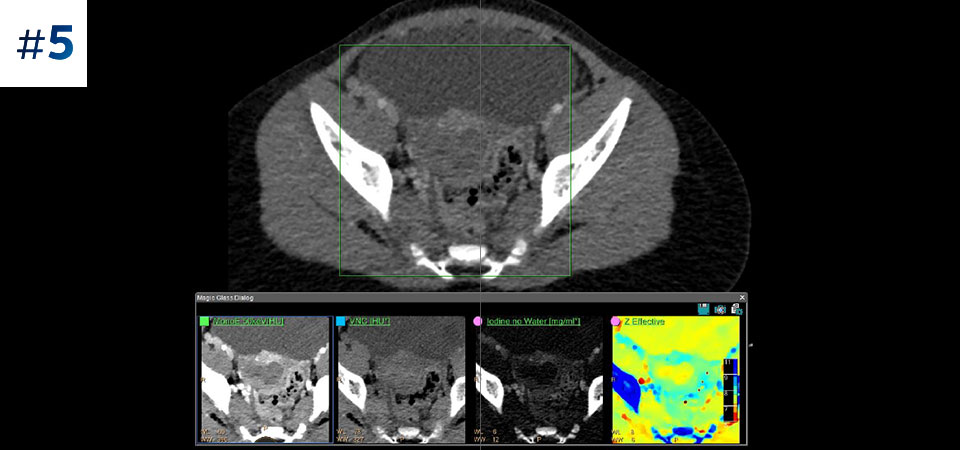

通常どおりにスキャン いつでもどの患者に対しても、1回の高速な低線量スキャンで標準データおよびスペクトラルデータを取得できます。

常に使用可能 スペクトラルデータは常に100%使用可能であり、検査結果はいつでも、オンデマンドだけでなく、レトロスペクティブに取得することもできます。

フォローアップ検査の削減 組織の特性評価と視覚化が改善されることにより、患者の検査が最適でなかった場合や、偶発病変が見つかった場合に、フォローアップスキャンを行う必要性が低減される可能性があります。

さまざまな患者タイプ 小児患者から肥満患者まで、幅広い患者タイプにメリットがあります。